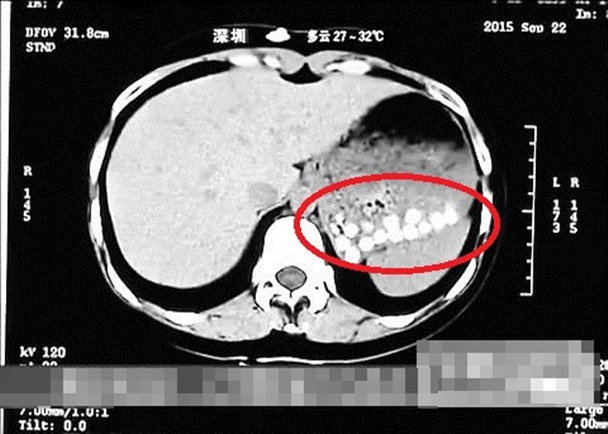

เรื่องดังกล่าวปูดขึ้นหลังจากผู้สื่อข่าวของรายการ Life Help ได้รับประทานชานมไข่มุกจากร้านแห่งหนึ่งไป แต่แล้วกลับป่วยต้องเข้าโรงพยาบาล ผลการตรวจซีทีแสกนพบว่า ในท้องของผู้สื่อข่าวรายนี้ มีเม็ดไข่มุกที่กินเข้าไป และยังคงสภาพเป็นเม็ด ๆ อยู่ไม่ยอมย่อย